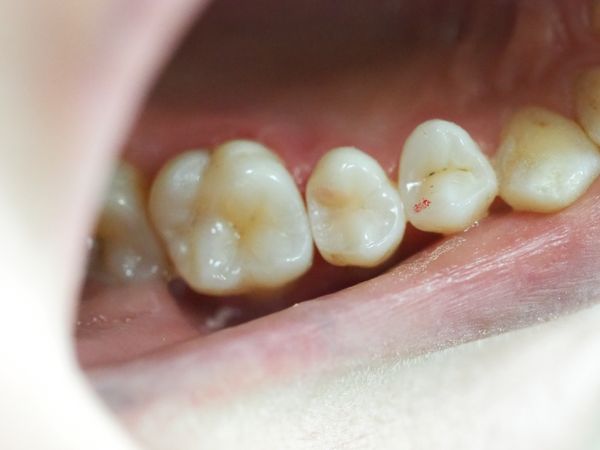

Обычный осмотр не выявил патологий, однако при детальном исследовании удалось выявить тёмный овал под эмалью верхнего правого премоляра (зуб 1.5) — контактный кариес, расположенный в тесном межзубном пространстве. Холодовая проба и обдув воздухом со стороны кариеса вызвал болевые ощущения.

Простукивание безболезненно, зуб неподвижен. Десна выглядела нормально, слизистая бледно-розовая и блестящая.